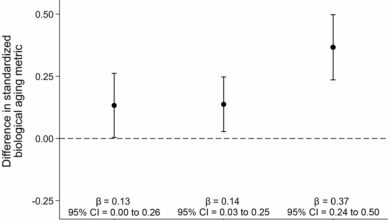

Sobreviventes de câncer de mama experimentam envelhecimento biológico mais rápido em comparação com mulheres sem câncer, segundo estudo

Análise de caso-controle do envelhecimento biológico e do status do câncer de mama. Resultados de modelos de regressão linear multivariada…